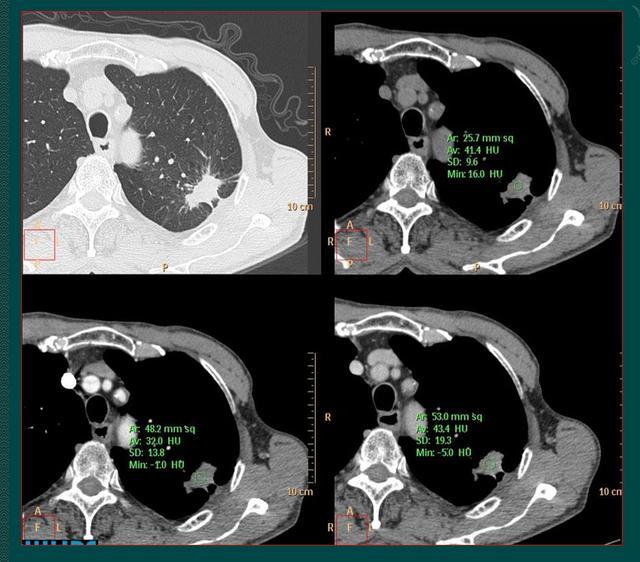

病人的儿子带着片子去找了黄教授会诊,黄教授建议先做个增强CT,看看病灶内有无血供。

1.陈旧性结核灶里面的血管会被结核杆菌破坏掉,增强扫描是不强化的(活动期可见强化,多为包膜样强化);

2.如果是肺癌,里面会有杂乱血管滋养癌细胞,增强CT多呈现轻中度不均匀强化,通过测量CT至可以明确。

老爷子后来预约了增强CT,显示病灶没有强化,动脉期和静脉期病灶密度没有增加,说明高密度的造影剂随血液循环过来后,进不去病灶内部,里面没有血管,提示为陈旧性肺结核。

为求万全之策,又做了经皮肺穿刺,发现肺结核特有的干酪样坏死物,没有癌细胞,老人避免了手术创伤。嗯,也省了一笔钱。

这个病例告诉我们,当从形态特点上无法鉴别肺结核与肺癌时,增强CT有时会提供有价值线索。